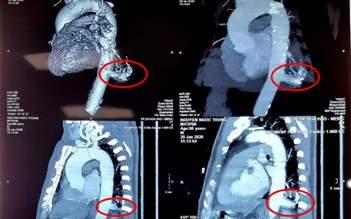

Dùng robot mổ cắt khối u, điều trị ung thư phổi